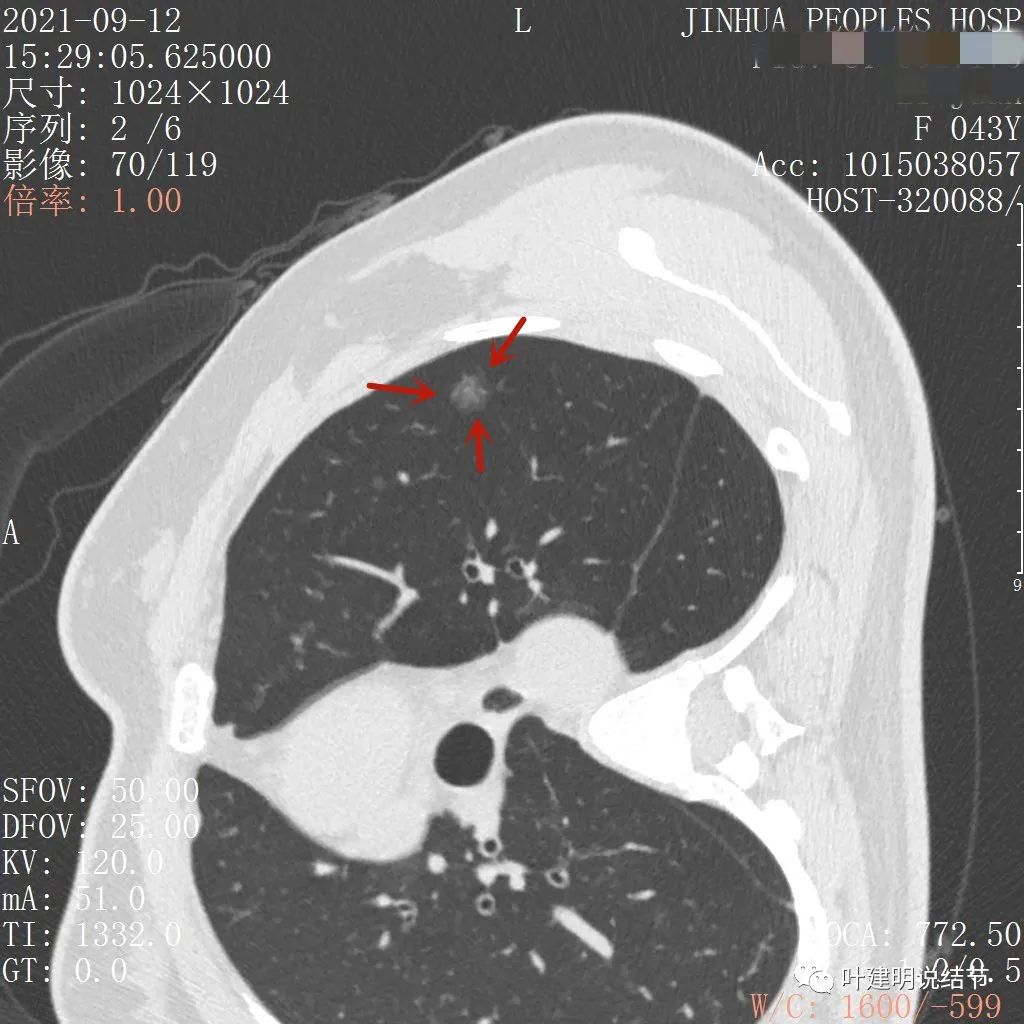

不均质的偏低密度磨玻璃结节,轮廓清

上图示病灶内部有高密度点状成分(粉色箭头所指)

同样示内部点状高密度,瘤肺边界清,密度显乱